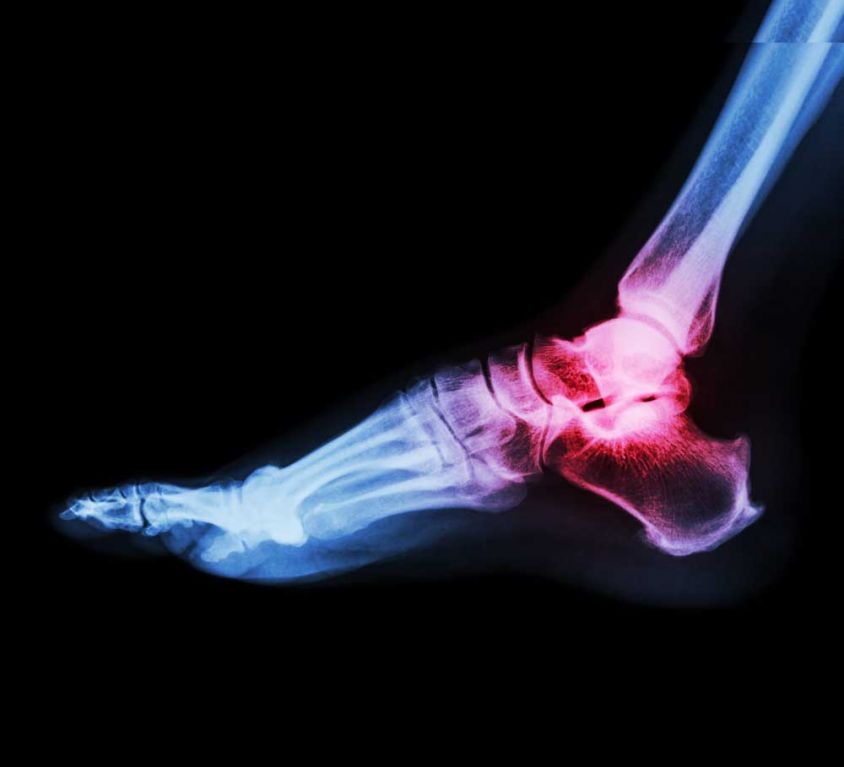

Foot and Ankle Procedures

Our surgeons are trained to treat all disorders of the foot and ankle, both surgical and non-surgical. Additionally, the surgeons are also trained to understand the complex connections between disorders and deformities of the foot, ankle, knee, hip, and the spine. Therefore, the surgeon will typically see cases that vary from trauma (such as malleolar fractures, tibial pilon fractures, calcaneus fractures, navicular and midfoot injuries and metatarsal and phalangeal fractures.) Arthritis care (primarily surgical) of the ankle joint and the joints of the hindfoot (tarsals), midfoot (metatarsals) and forefoot (phalanges) also plays a rather significant role. Congenital and acquired deformities include adult acquired flatfoot, non-neuromuscular foot deformity, diabetic foot disorders, hallux valgus and several common pediatric foot and ankle conditions (such as clubfoot, flat feet, tarsal coalitions, etc.)